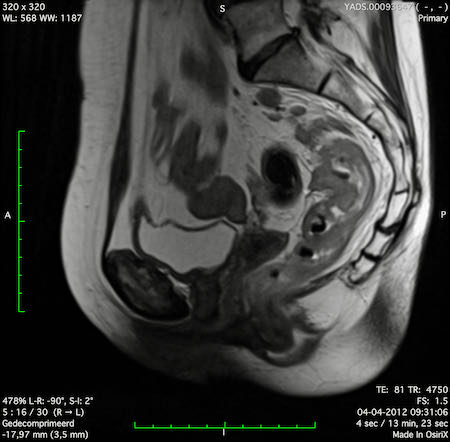

Hình ảnh

Các hình ảnh được cung cấp cho thấy ung thư biểu mô tế bào nhẫn với tình trạng dày lan tỏa thành trực tràng, hình ảnh bia bắn điển hình, và sự xâm lấn mỡ mạc treo trực tràng.